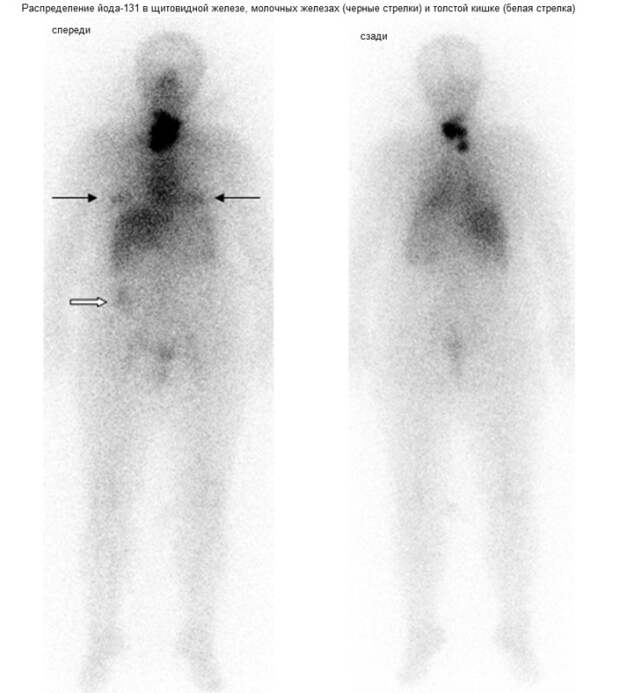

Йод-131 с периодом полураспада 8 суток дает стабильный ксенон-131, поэтому уже через несколько месяцев уровень загрязнения не определяется детекторами. С другой стороны, высокая скорость полураспада оборачивается высокой удельной активностью бета-излучения, которое оказывают основное повреждающее воздействие на живые ткани в радиусе 1-2 мм от атома изотопа. Таким образом, селективное накопления йода-131 в клетках щитовидной железы и малый радиус бета-излучения обуславливают практически исключительное воздействие изотопа в пределах данного органа.

Эти особенности изотопа позволили создать на его основе химиопрепараты, с помощью которых прицельно уничтожаются все клетки щитовидной железы при лечении онкологических заболеваний данного органа. Однако в случае радиоактивного загрязнения йод-131 накапливается в щитовидной железе здоровых людей в меньших дозах, поэтому не уничтожает орган, а вызывает в его клетках точечные мутации генов. Например, такая мутация может затронуть гены, отвечающие за регуляцию клеточного деления, созревание или гибель клетки, что может превратить ее в раковую.